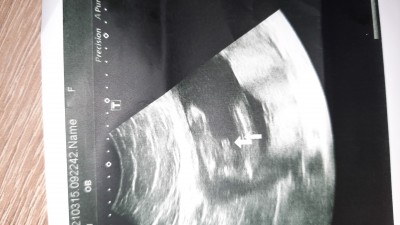

Burda doktor pipiyi mi göstermek istemiş . Erkek dedi ama yine de tecrübeli annelerden yorum almak istedim şimdiden teşekkürler.

Gebelik haftası 20

Evet pipiyi göstermiş benimde böyle bir ultrason kağıdım var

Alttan çekmiş galiba değil mi .

Erkek erkek evet oda pipi hayirli olsun

Kuzum erkek hayırlısı olsun yiğidin malı meydandadır demiş sermiş herşeyi öne senin yavrucak☺️